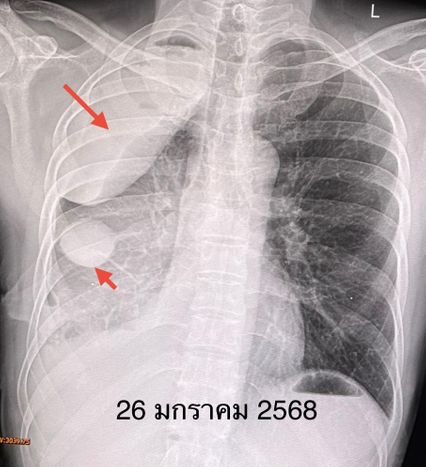

หลังกินยา osimertinib 3 สัปดาห์ ผู้ป่วยดีขึ้น อาการเหนื่อยและปวดกระดูกลดลง เอกซเรย์ปอด พบก้อนเลือดในเยื่อหุ้มปอดหายไป น้ำในช่องเยื่อหุ้มปอดลดลง